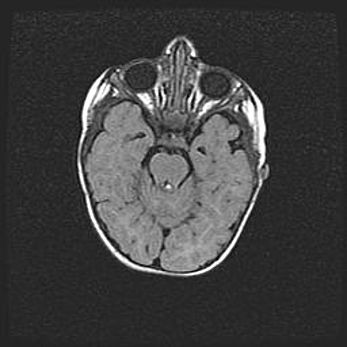

Церебральная ишемия II.

Возраст: 5 дней

Вес: 3400 г

Пол: женский

Окружность головы: 35 см

Срок гестации: 39 недель

Церебральная ишемия – это заболевание, характеризующееся недостаточностью (гипоксией) либо полным прекращением (аноксией) снабжения мозга кислородом по причине закупорки одного или нескольких сосудов. Это приводит к  что метаболическим расстройствам различной степени тяжести в тканях головного мозга, развитию коагуляционных некрозов и гибели нейронов.